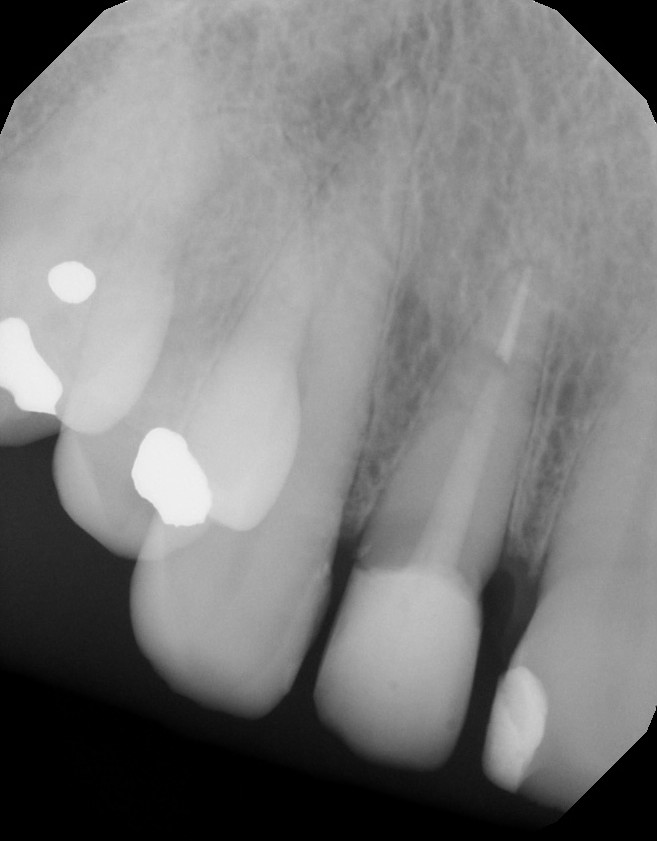

From www.midtownendodontistnyc.com

Root Canal Before & Afters Midtown Endodontist NYC Post And Core Before And After Understanding the indications, materials, techniques, and factors affecting success is crucial for dental professionals. The first stages are common for both prefabricated and cast post and cores. Post and core procedure is painless and does not even require local anesthesia as the tooth has long been dead after the root canal treatment. When a significant portion of a tooth’s structure. Post And Core Before And After.